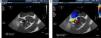

Valsalva sinus pseudoaneurysms are uncommon. The main causes for the formation of pseudoaneurysms are endocarditis, previous enlargement of the aortic root, aortic regurgitation and the use of a composite graft. We report the case of a 79-year-old man with an aortic bioprosthesis implanted five years ago to treat severe aortic regurgitation (AR) with a normal aortic root. A new diastolic murmur was heard in the last clinical review, so the patient was referred for transthoracic echocardiography, which demonstrated severe AR and a dilated aortic root. Transesophageal echocardiography (Figures 1 and 2) confirmed severe AR with an aneurysmal dilatation of the non-coronary sinus, with no signs of infection. Computed tomography (CT) confirmed severe dilatation of the aortic root (Figure 3, arrows). During surgery, a transverse fissure was detected in the intima of the non-coronary sinus. The valve was replaced with a 27-mm valve and the aortic root was remodeled using a 30-mm vascular graft.